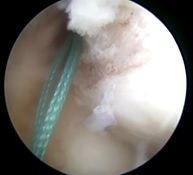

![]() | ![]() | ![]() |

| 大腿骨孔作成 | グラフト挿入 | 再建靱帯 |